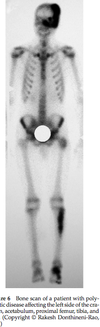

Bone scan

- required as part of staging workup - will show very “hot” lesion

Bone scan - hot

- __assess mets

- Bone Scan - skip lesions, boney mets